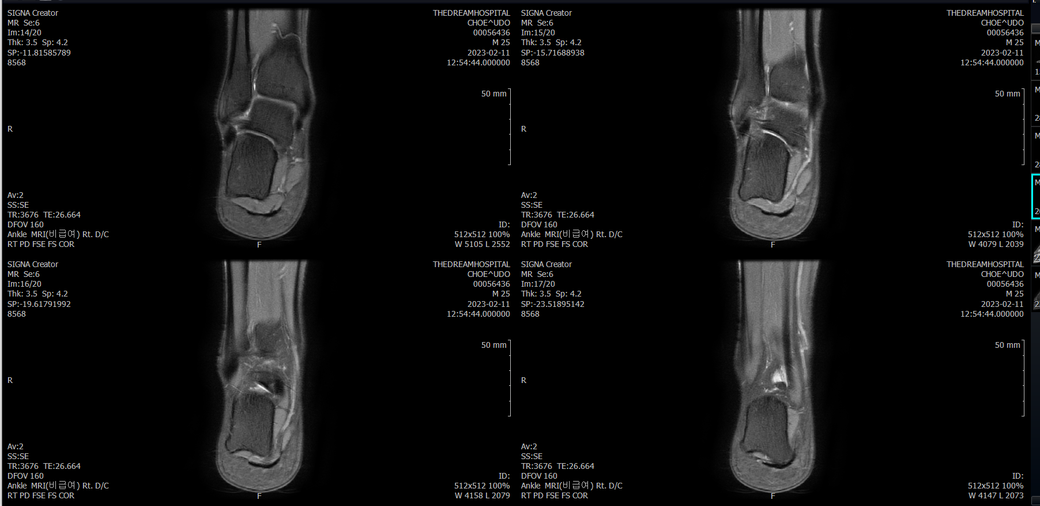

오른발목 mri 전체사진입니다. 제가 병원을 갈수없는상황인지라.... 봐주시면 감사하겠습니다.

엑스레이에서는 문제가 없다고 하여 오른발목 mri촬영했습니다.

우선 전반적으로 봤을 때 큰 이상은 없어보입니다.

전거비인대 등도 저명한 손상은 없는 것 같아 보이지만, 어느 부분의 통증 등으로 인해 촬영을 하셨는지 말씀을 해주신다면 보다 정확한 병변파악이 가능하겠으며, 병원에서 판독이 완료되신다면 전화 등으로 문의를 해보시는 것이 좋겠습니다.